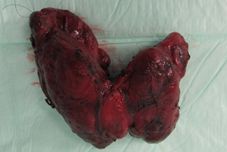

Thyroid Gland

The thyroid gland, usually configured like a butterfly, lies below the larynx adjacent to the trachea. The crucial element for the synthesis of the thyroid hormones thyroxine (T4) and triiodothyronine (T3) is iodine. It is absorbed in the intestine through food and is accumulated in the thyroid gland. The daily iodine requirement of humans is about 150 µg. Thyroid function is controlled by the pituitary gland. This produces TSH (thyroid stimulating hormone), which has an activating influence on hormone production in the thyroid gland as well as hormone release into the bloodstream.